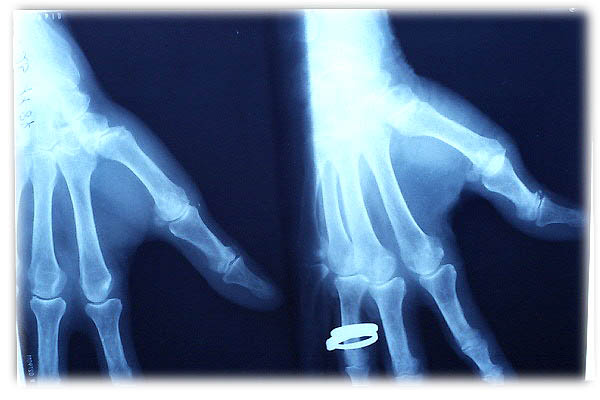

ACT Alteraciones degenerativas en muñeca.